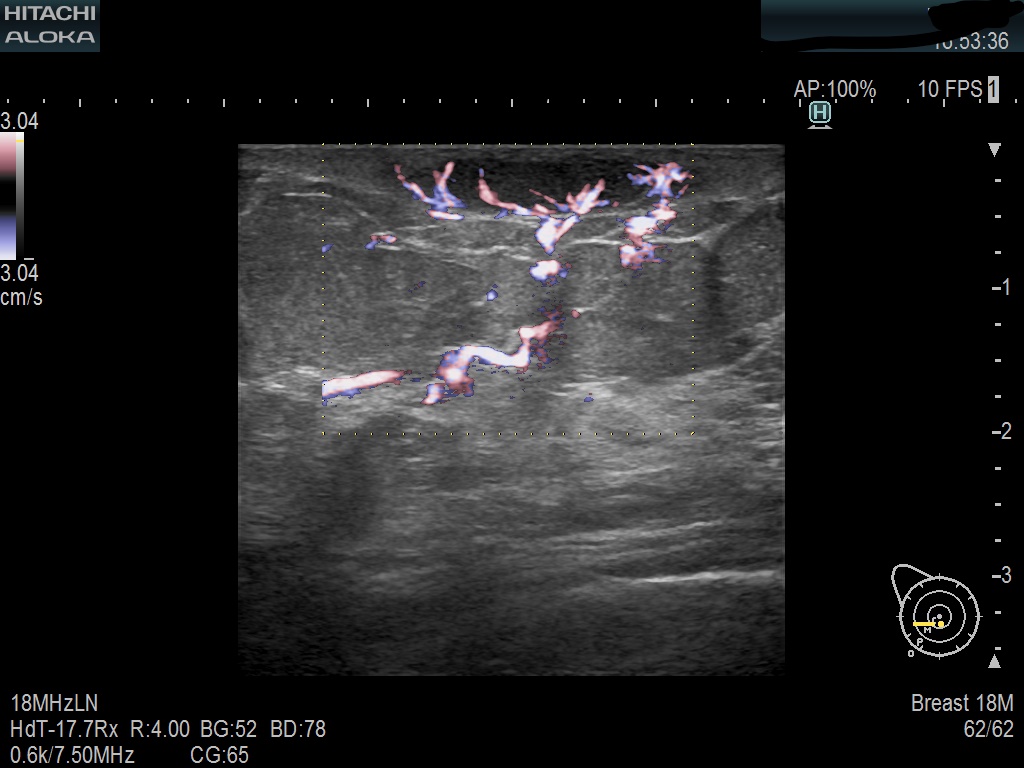

Superior guidance for all applications

Fujifilm Healthcare Americas is committed to designing tools that help surgeons navigate inside the human body and provide the necessary information to immediately make critical surgical decisions.

Fujifilm Healthcare's dedication to Surgeons provides outstanding ultrasound technology, professional support and the specialized tools necessary to best perform comprehensive real-time ultrasound imaging in Breast Surgery, General Surgery, Laparoscopic Surgery, Neurosurgery, Robotic Surgery and Surgical Oncology.